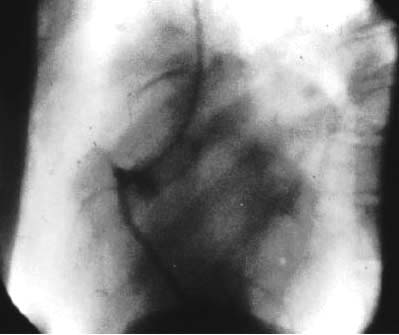

図1. Forssmannが行なった自己人体実験.左上肢静脈から右心房に挿入されたカテーテルが見える.

【要旨】 緊急時の心腔内薬剤投与法の新しい方法として,静脈系から右心系へのカテーテル挿入を試みた.屍体による実験を経て,自らを実験台としてこれを試した.肘静脈を穿刺し,ここから尿管カテーテルを挿入した.カテーテルの移動に伴い軽度の温感を感じた他は副作用はなかった.カテーテルを挿入した状態でレントゲン撮影室に移動して撮影したところ,カテーテルが右心房に達していることを確認した(図1).

臨床例として,高度の循環障害の患者の心腔内にこの方法でアドレナリンなどの薬剤を投与し,症状の改善をみた.かくして,右心系へのカテーテル挿入は安全であることが証明できた.